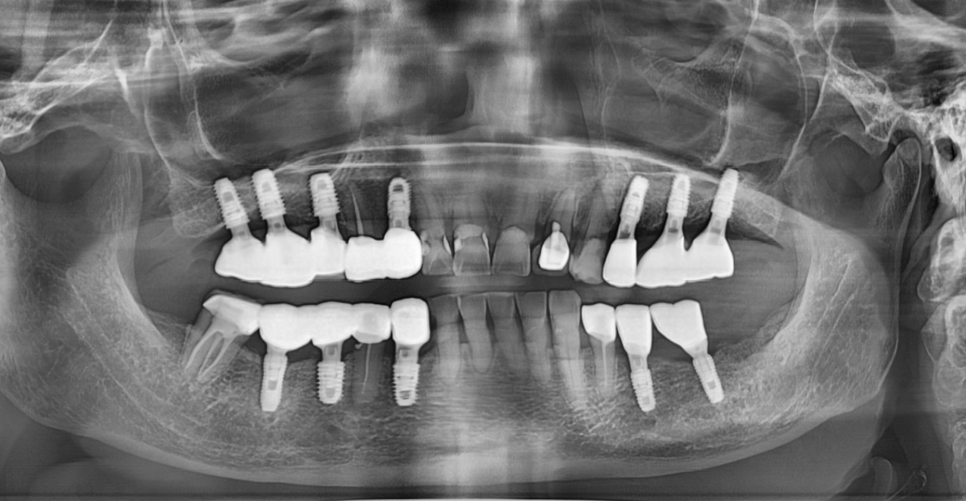

다른 병원에서 시술받은 임플란트라도

충분히 수리하고 오래 사용할 수 있는 경우가 많습니다.

240118

| 1) 브랜드를 알고 |

|---|

| 2) 임플란트 자체에 문제가 없으며 |

| 3) 주변 잇몸 및 뼈가 건강한 경우 |

수리가 가능하다는 것

제일 좋은 것은 망가지기 전, 손쓸 수 있을 때 점검받는 것이

임플란트 수명을 지키는 가장 확실한 방법입니다